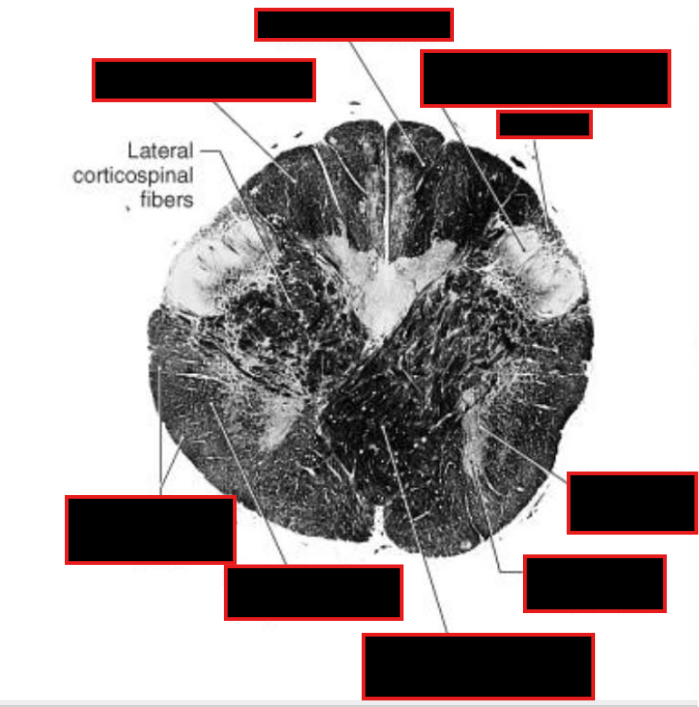

Describe Sensory Decussation of the Dorsal Columns:

Pathway? Locations?

What are the names of the fibers decussating?

Sensory Decussation of Dorsal Column

Dorsal Columns → ascend to caudal medulla → synapse @ gracile/cuneate nucleus

Location: deep to gracile tubercle (clava) and cuneate tubercle

dorsal column nuclei → Decussates @ tegmentum → medial lemniscus → ascend to thalamus (VPL).

Fibers Decussating = internal arcuate fibers

Fibers ascending in medial lemniscus = somatotopically organized

Describe what happens to these tracts @ level of sensory dessucation:

tectospinal tract + medial longitudinal fasciculus

uncrossed pyamidal tracts

Spinocerebellar Tract, anterlateral system, rubrospinal tract

located in midline behind medial lemniscis

located ventromedially.

moved to a slightly more posterior position